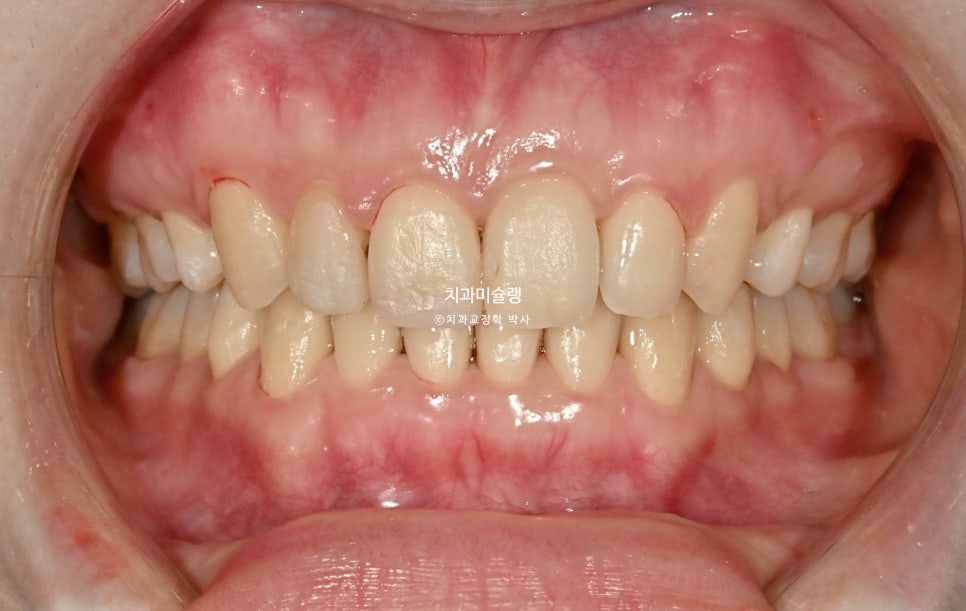

초진사진에서는 가운데 앞니가 커보였으나 교정후 사진에서 가운데앞니가 작아진것처럼 보이죠.

하지만 앞니 사이즈가 작아진게 아니라, 튀어나와있던 앞니가 뒤로 들어가며 비로소 본래 사이즈로 보이는것이랍니다.

2023.04-2026.01

사랑니까지 물샐틈 없는 교합을 보입니다.

이제 안모 비교 보겠습니다.